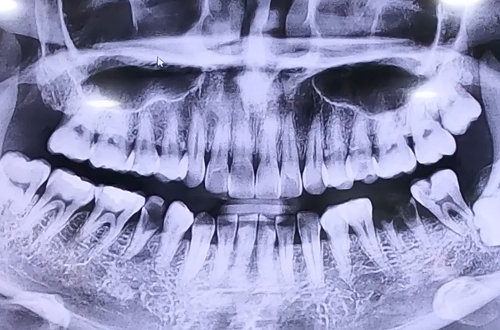

BEFORE

충치로 인해 이를 빼고 당일 즉시 임플란트를 진행한 사례입니다.

환자분은 오른쪽 아래 작은 어금니 1개, 왼쪽 아래 큰 어금니 2개가

심한 충치로 인해 많이 약해지고 손상된 상태로, 복원이 불가하여 발치를 결정하였습니다.